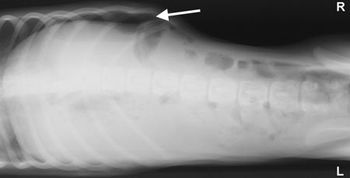

If ultrasonography is the hot guy you met online, abdominal radiography is your adorable high school sweetheart. Metaphors aside, Dr. Anthony Pease says abdominal radiographs are a rapid, readily available method to give a valuable overview of the abdomen.